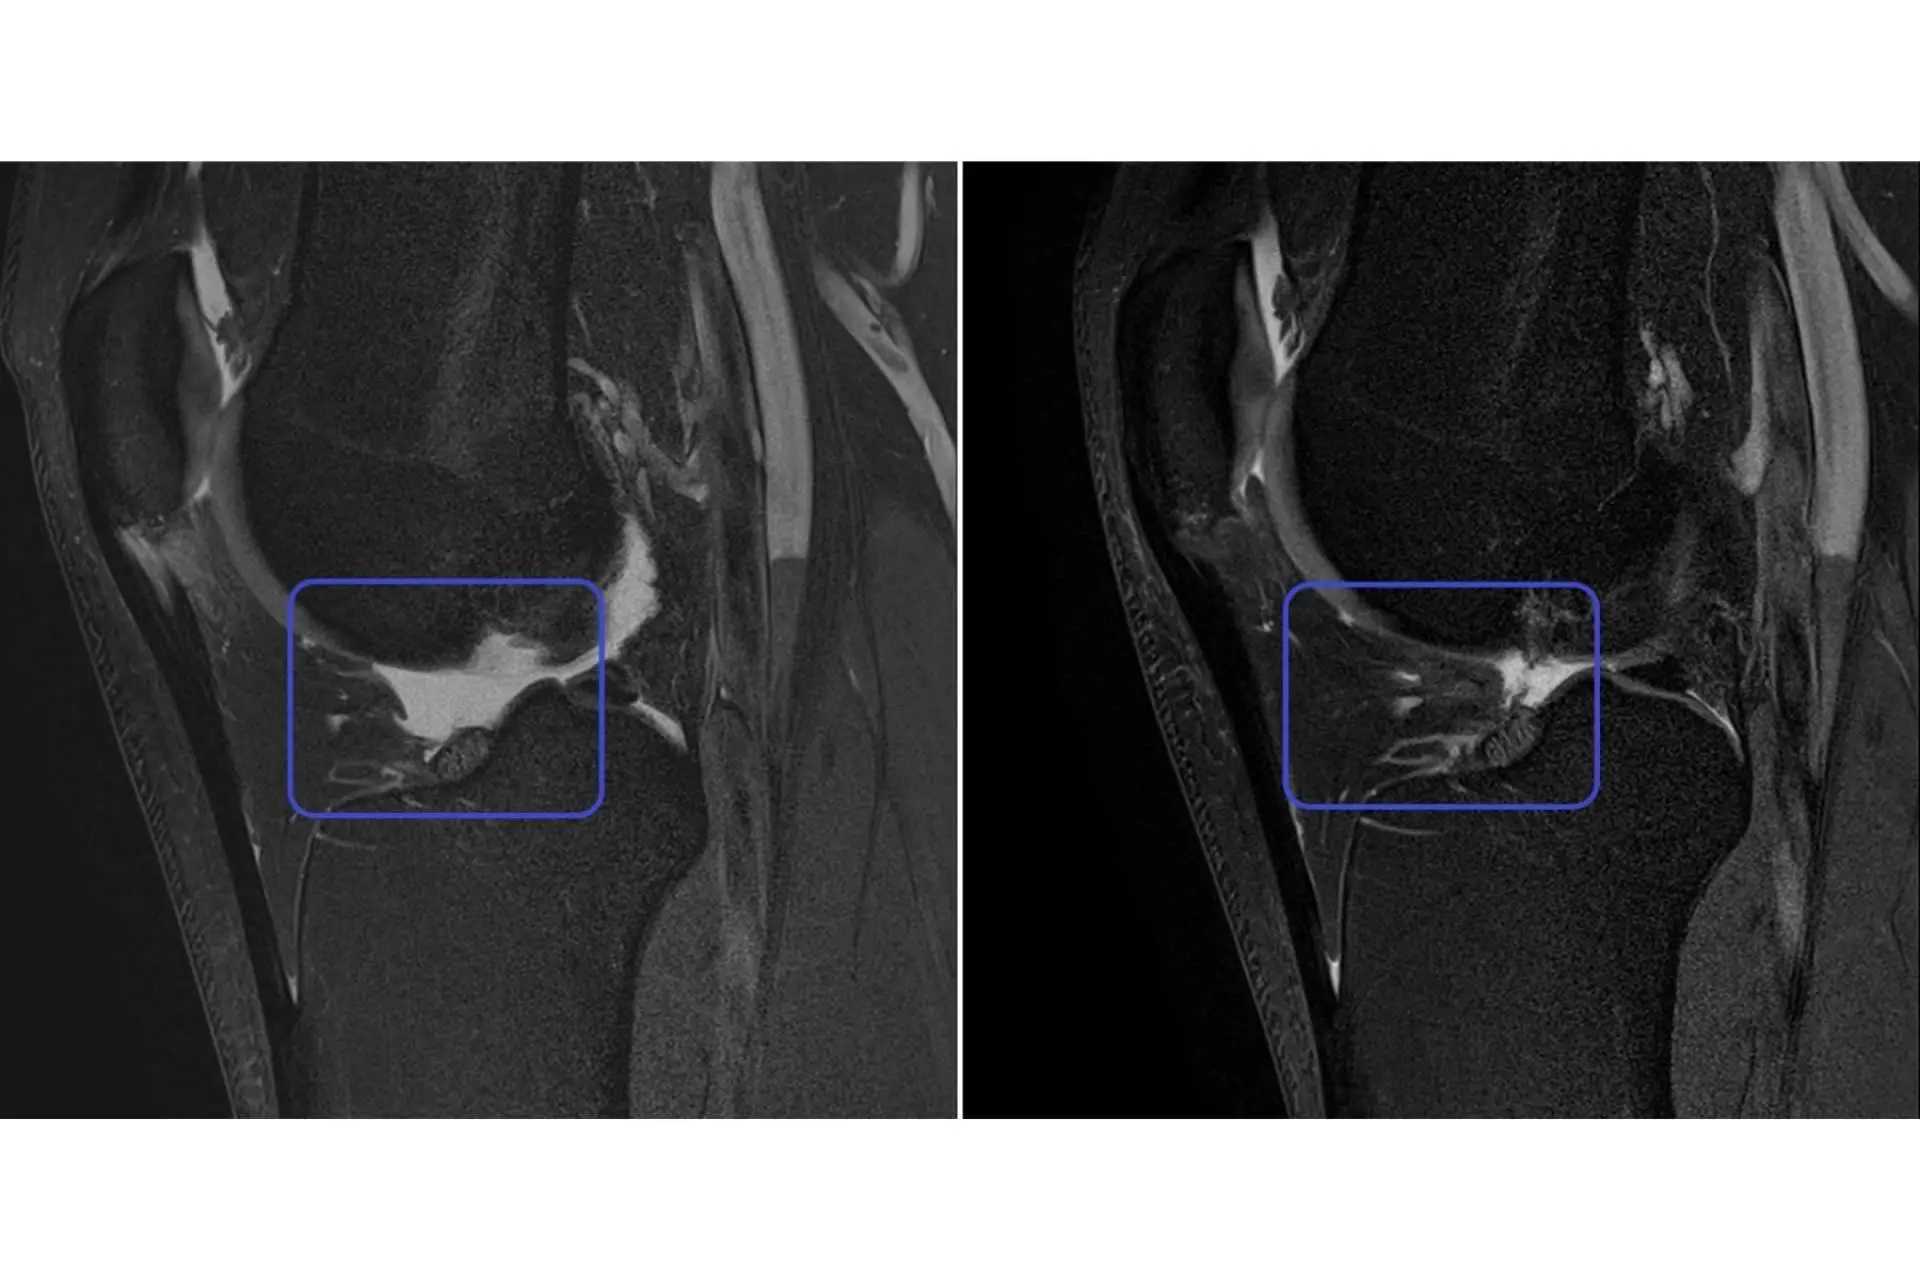

Por su parte, el segundo grupo se trató con una solución de PRP (Plasma Rico en Plaquetas), es decir, se obtuvo sangre periférica que fue centrifugada y aplicada siguiendo el mismo procedimiento. Ambos grupos siguieron tratamiento ambulatorio, sin ingreso hospitalario, y los resultados fueron medidos a nivel clínico con las escalas EVA y VISA-P y a nivel de imagen por ecografías, UTC y Resonancia Magnética 3 Tesla (alta resolución).

A los 6 meses, el grupo tratado con células madre mesenquimales cultivadas mostró por primera vez la restauración de la estructura del tendón hasta recuperar un 40% de la lesión en el 100% de los pacientes, mientras que el grupo tratado con PRP no mostró ni evolución ni regeneración y acabaron recayendo de su lesión.